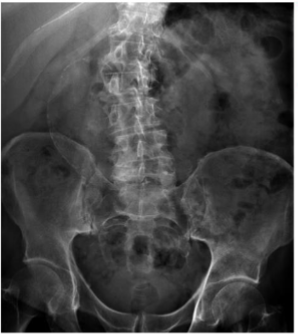

What is this and what type of scan

AAA, Abx